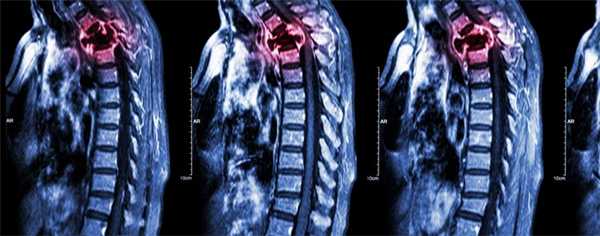

Патологические переломы возникают при разрушении более 50% кортикального слоя. Чаще всего выявляются в позвонках, второе место по распространенности занимают переломы бедренной кости, обычно - в области шейки или диафиза. Отличительной особенностью патологических переломов позвоночника при метастазах в кости является множественность поражения (одновременно выявляется нарушение целостности нескольких позвонков). Как правило, страдает грудной или поясничный отдел. Повреждения могут сопровождаться компрессией нервных корешков или спинного мозга.

Причиной патологического перелома при метастазах в кости может стать незначительное травмирующее воздействие, например, слабый удар или даже неловкий поворот в постели. Иногда такие переломы выглядят спонтанными, то есть, возникшими без каких-либо внешних причин. Перелом может сопровождаться смещением отломков. Нарушения функции конечностей при переломах длинных трубчатых костей и неврологические расстройства при переломах позвоночника становятся одним из ведущих факторов ухудшения качества жизни больного.

Компрессия спинного мозга

Компрессия спинного мозга выявляется у 1-5% пациентов с метастатическими поражениями позвоночника. В 70% случаев причиной нарушений становятся метастазы в грудные позвонки, в 20% - в поясничные и крестцовые позвонки, в 10% случаев - в шейные позвонки. При метастазах в кости могут выявляться как острые (при сдавлении костным фрагментом), так и постепенно прогрессирующие (при сдавлении растущей опухолью) расстройства. При сдавлении растущим новообразованием пациентов с метастазами в кости беспокоят нарастающие боли. Развивается мышечная слабость, выявляются нарушения чувствительности. На заключительной стадии возникают парезы, параличи и нарушения функции тазовых органов.

При сдавлении фрагментом кости клиническая картина компрессии спинного мозга развивается внезапно. На начальных стадиях оба вида компрессии обратимы (полностью или частично). При отсутствии своевременной медицинской помощи в течение нескольких часов или дней паралич становится необратимым. Своевременное адекватное лечение позволяет уменьшить выраженность симптомов, однако восстановление способности к самостоятельному передвижению отмечается всего у 10% больных с уже развившимся параличом.

О наличии онкологического заболевания свидетельствует положительный анализ крови на онкомаркеры. На начальном этапе диагностики больным с подозрением на метастазы в позвоночник назначают рентгенографию позвоночника. На ранних стадиях метастазирования рентгенологические признаки поражения позвонков могут отсутствовать, поэтому при отрицательном результате исследования пациентов с подозрением на метастазы в позвоночник направляют на сцинтиграфию, КТ и МРТ позвоночника. Для выявления первичной неоплазии и вторичных очагов проводят УЗИ органов брюшной полости, рентгенографию органов грудной клетки, маммографию и другие диагностические процедуры. Дифференциальную диагностику метастазов в позвоночник осуществляют с сосудистыми поражениями, последствиями воспалительных заболеваний, вторичной демиелинизацией и первичными неоплазиями позвоночного столба.